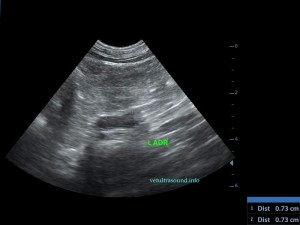

Ήπια ηπατομεγαλία με αύξηση της ηχογένειας του οργάνου, χωρίς παρουσία εστιακών αλλοιώσεων(pic.4). Πάχυνση του τοιχώματος της χοληδόχου κύστης με εικόνα βλεννοκήλης ( kiwi sign) και έντονη υπερηχογένεια στη περιοχή περί αυτού(pic.1&2). Ήπια διάταση της νεφρικής πυέλου, πιθανόν λόγω της πολυουρίας και πολυδιψίας(pic.3). Επασβέστωση στον οπίσθιο πόλο του δεξιού επινεφριδίου και αύξηση των διαστάσεών του(pic.6). Απουσία ασκιτικής συλλογής και παθολογικά διογκωμένων λεμφαδένων.